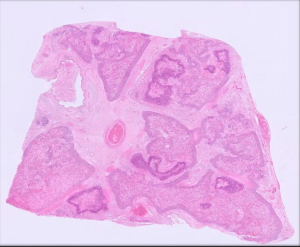

Figure 1: Section of lung from a heifer showing extensive inflammation and necrosis typical of Mannheimia haemolytica fulminating pneumonia.